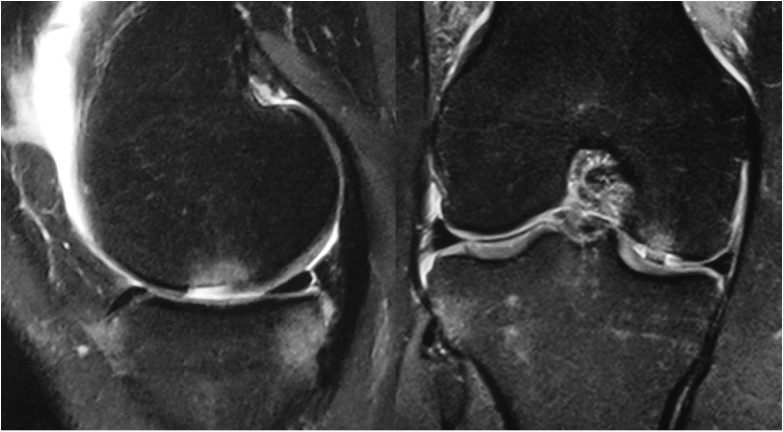

Le diagnostic est évoqué cliniquement et sur un bilan radiographique standard.

L’arthroscanner, l’IRM et l’arthro-IRM permettent d’apprécier plus précisément la largeur sur les coupes frontales et la longueur sur les coupes sagittales

L’arthroscopie permet une évaluation de la profondeur des lésions.